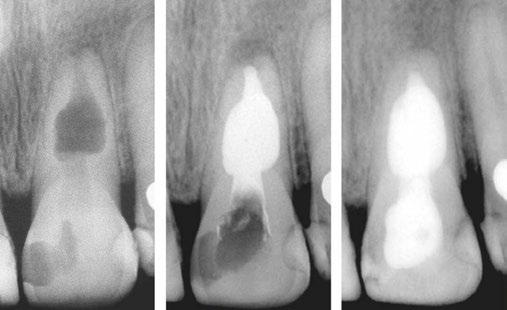

Figures 1A-1C: 1A. Preoperative X-ray. 1B. Immediate postoperative X-ray. 1C. Follow-up after 9 years and 10 months

Periapical radiographs and medical records corresponding to 48 teeth with IRR were collected from five different dental offices. The following aspects of the IRR were then analyzed: number of tooth in which it was found, location, presence or absence of periapical radiolucency, shape of the affected dentin walls, type of treatment performed, filling technique used, degree of adaptation of the filling to the resorption, presence of perforation communicating with the periodontium. Of the 48 cases diagnosed with IRR, all have been endodontically treated, and 29 of them have received initial treatments and 19 retreatments. Of the total number of cases, 29 had long-term follow-ups, while 19 do not have them.

Of the total, 29 had long-term radiographic follow-ups that ranged from a minimum of 6 months to a maximum of 25 years, with an average of 5 years, 4 months. Of the cases with radiographic follow-ups, 28 were considered successful and one failure (Table 2). Of the successful cases, 17 corresponded to treatments and 11 to retreatments (Figures 1A, 1B, 1C, and 2A, 2B, 2C). The tooth considered failed was a retreatment.

The radiographic appearances that generates the IRR are varied. The most common one observed in the present study was a circular shape with regular and symmetrical walls specially in single-rooted teeth (Figure 4A), although there were also some

Figures 2A-2C: 2A. Preoperative X-ray. 2B. Immediate postoperative X-ray. 2C. Follow-up after 18 years and 6 months

Figures 3A-3C: 3A. Preoperative X-ray. 3B. Immediate postoperative X-ray. 3C. Follow-up after 4 years

irregular ones with asymmetrical walls (Figure 4B). In molars, when resorption affects the pulp chamber, it was commonly seen as an irregularly shaped radiolucent cavity2 (Figure 4C).

Figure 4A-4C: 4A. Maxillary lateral incisor with an internal resorption at the coronal third. 4B. Mandibular canine with an internal resorption in the middle-apical area. 4C. Mandibular molar with an irregular internal resorption in the coronal portion Figures 5A-5C:

5A. Preoperative X-ray. 5B. Immediate postoperative X-ray. 5C. Follow-up after 1 year and 9 months EP